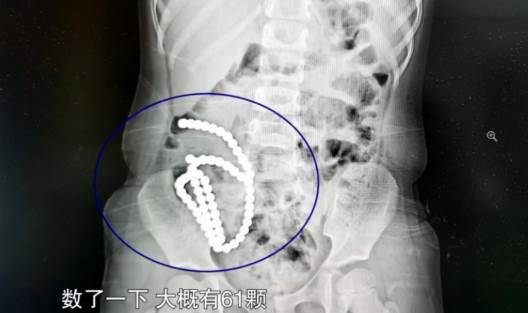

經過將近2小時的手術,醫師將多達61顆磁力珠從女童的腸胃裡取出。

副院長兼腔鏡中心主任高志剛醫師表示,女童並非一下子把磁力珠通通吞下肚,而是分次慢慢誤食。前後吞下去的珠子因為磁力相吸,「2顆巴克球之間就會有腸管壁夾在中間,慢慢腸子就穿孔了」。高醫師說明把磁力珠取出後,女童的腸壁破了14個洞,雖然手術成功修補,但仍對健康造成極大的損害,「一輩子腸沾黏、腸梗阻的風險都很大」。